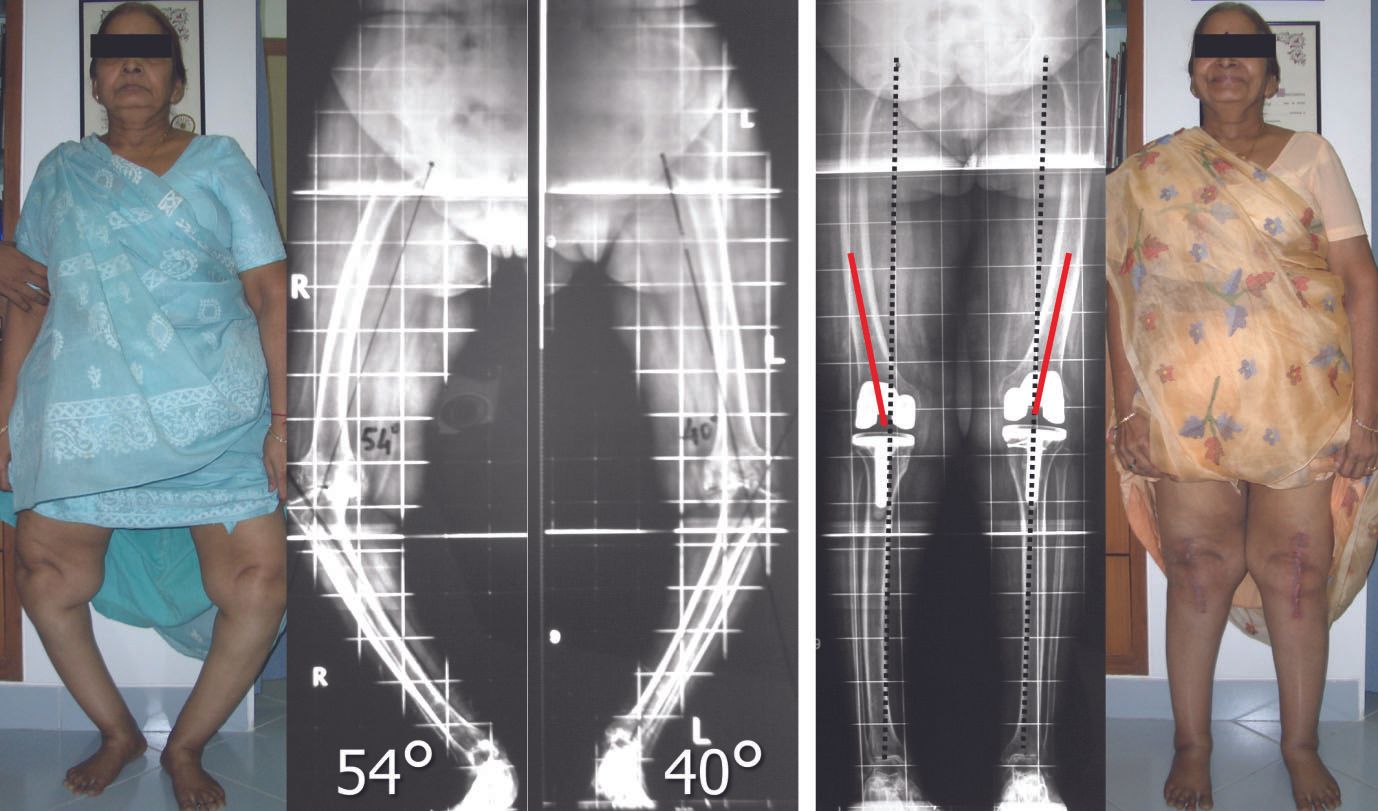

The author has performed over 12000 total knee replacements, over 6000 with computer navigation and has made several observations which are published in scientific studies 1-12. Here is the method followed which has satisfactorily achieved alignment and balance without requiring release of the superficial medial collateral ligament2 and without using constrained implants (only posterior cruciate substituting designs have been used in almost all cases)(Fig 1).

5. Flexion of the knee relaxes the posterior soft tissues and excludes them from contributing to medio-lateral imbalance

If extra-articular deformity (EAD) is >20 degrees, close to the joint, and resection likely to damage LCL attachment or if the distal tibial axis falls outside of tibial plateau, then EA osteotomy may be required.(Figs 4-6)